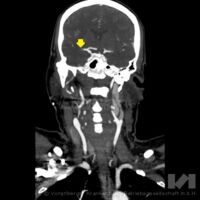

Bei Patienten mit eindeutigem Schlaganfall, die sehr schnell in ein Zentrum kommen, besteht die Möglichkeit, nach der klinischen Diagnose des Schlaganfalls und der Untersuchung mit Computertomographie (CT) oder Magnetresonanztomographie (MRT) das erwähnte Blutgerinnsel mittels einer Infusionstherapie (="Lysetherapie)" zu lysieren, also aufzulösen. So kann das zuvor verstopfte Blutgefäß wieder durchgängig gemacht und der Sauerstoffmangel aufgehoben werden. Dies ist jedoch nur innerhalb der ersten 4,5 Stunden nach Beginn der Symptomatik möglich. Und: je früher behandelt wird, umso besser wirkt die Therapie! Allerdings kann ein großes (über 8mm langes) Blutgerinnsel nur sehr selten durch die Lyse aufgelöst werden.

Hier besteht bei einem Teil der Patienten die Möglichkeit, das Blutgerinnsel mechanisch mittels eines Katheters - ähnlich dem Herzkatheter - zu entfernen: Das Gerinnsel wird direkt über ein Maschengitter (ein 4-6 mm großer sog. Stent) herausgezogen oder abgesaugt. „Katheter werden - innerhalb der ersten 6 Stunden nach dem Schlaganfall - mittels eines Microkatheters über die Leiste bis in das Gehirn des Patienten vorgeschoben, und zwar an jene Stelle, an welcher das Blutgerinnsel (Thrombus) die Schlagader im Hirn verstopft. Dort wird der Stent geöffnet, das Gerinnsel bleibt im feinen Metallnetz hängen und kann mittels Katheter herausgezogen und aus dem Körper entfernt werden (= Ektomie - Herausschneiden, Herausholen)“, führt der interventionelle Radiologe OA Dr. Thomas Haglmüller, Experte in der interventionellen Behandlung von Schlaganfällen, aus. Die Thrombektomie ist somit eine mechanische Methode, um die Gefäße zu eröffnen. Eine Behandlung kann zwischen 30 Minuten und 2 Stunden dauern. Dieses Vorgehen ist durch Studien bestätigt worden. Voraussetzungen, um eine Thrombektomie durchführen zu können, ist neben der Größe des Gerinnsels aber auch seine Lage: Die Therapie ist nur dann anwendbar, wenn das Gerinnsel die größeren Arterien im Gehirn verschließt - sie ist somit nicht für alle Hirnregionen geeignet. „Mit der Thrombektomie können wir große Gefäße im Gehirn schneller und vor allem effizienter eröffnen, um die Schädigung zu verringern“, erklärt Dr. Haglmüller. Seit 2 Jahren steht Schlaganfall-Patienten in Vorarlberg diese neue Behandlungsmethode zur Verfügung, insgesamt werden jährlich 40-50 Patienten mittels dieser Methode erfolgreich behandelt. Wichtig ist, dass die Betroffenen rechtzeitig bzw. ohne Verzögerung ins Zentrum gebracht werden. Nur so haben sie eine Chance!